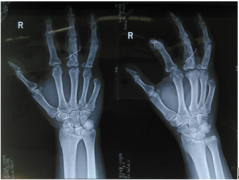

手足外科--成功实施济宁地区首例掌指关节置换术

近日,济宁市第一人民医院手足外科为一名饱受手指关节炎困扰患者...